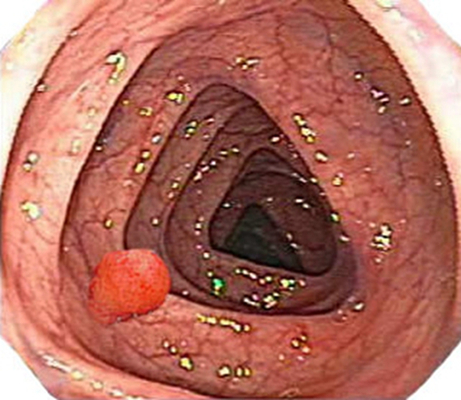

肛門癌圖片

肛癌早期症狀